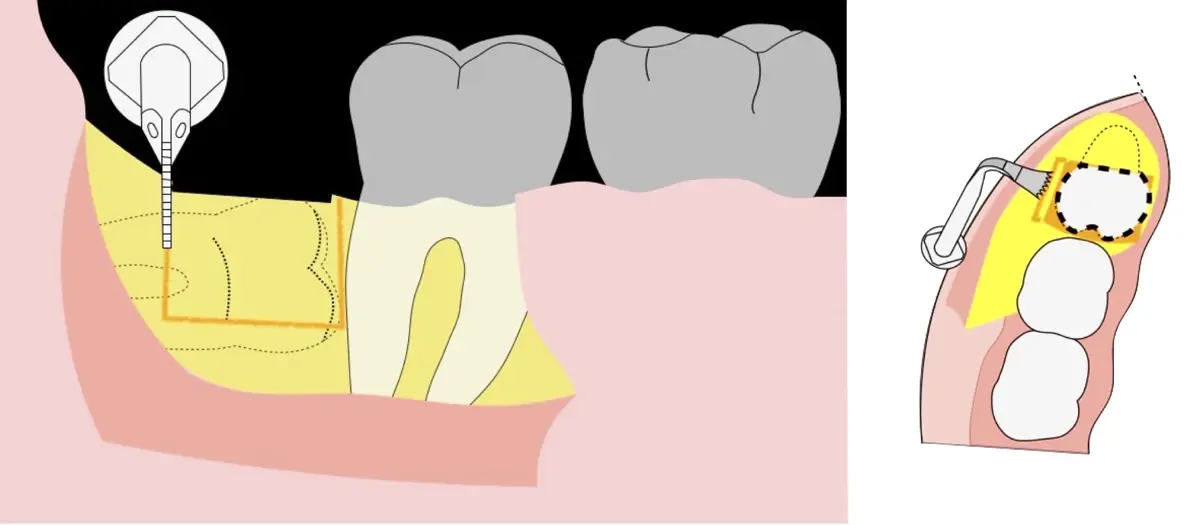

Es imprescindible conocer la ubicación de la tercera molar. Se puede emplear, adicionalmente a la evaluación clínica, herramientas radiográficas (panorámica y periapical) y tomográficas (Cone beam) para determinar la posición, grado de retención y proximidad a estructuras vecinas de riesgo como el nervio dentario inferior y así evitar lesiones (Figura 1).

El procedimiento se inicia colocando anestesia troncular para bloqueo del nervio dentario inferior y sus ramas. Luego, se establecerá el diseño de acceso según la disposición de la molar a extraer. Para fines didácticos, se explicará cómo se realizaría la extracción de la molar de la Figura 1: se realiza una incisión horizontal a nivel de la zona retromolar hasta llegar a distal de la segunda molar, continuándose con una incisión intrasurcular hasta mesial de la segunda molar, finalizando con una incisión vertical a espesor total hasta llegar a la línea mucogingival (Figura 2).